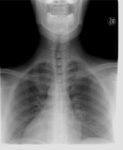

李綜合醫院神經內科醫師張峻誠說,一名婦人右側中大腦動脈阻塞而影響到視野 一名婦人右側中大腦動脈阻塞而影響到視野